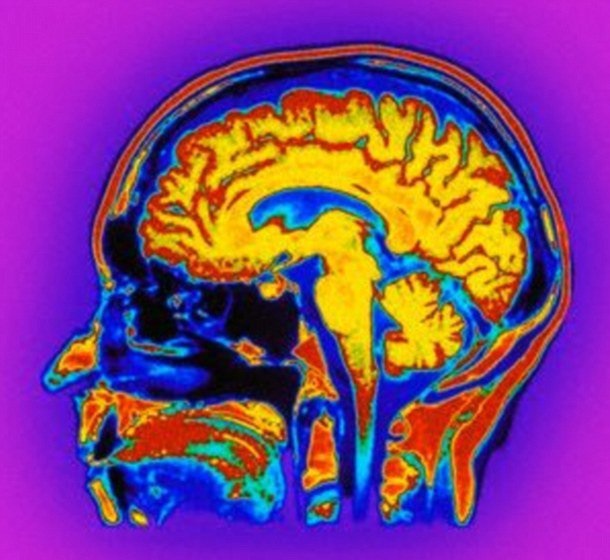

دو ساعت بعد که اثر دارو از بین رفت، بیمار مذکور مجددا به حالت پیشین با کمترین هوشیاری بازگشت. پزشکان چند هفته بعد مجددا به SV داروی میدازولام دادند و اینبار رفتار و خوانش‌های نوار مغزی وی را مورد بررسی قرار دادند. بررسی‌ها نشان داد که مصرف این دارو باعث تغییر در فعالیت امواج مغزی در دو ناحیه مغز بیمار می‌شد.

بخش اول مغز موسوم به شبکه کار مثبت است که به انسان در واکنش به وظایفی کمک می‌کند که نیازمند توجه فرد است.

بخش دومی مشئول تکلم و فهم زبان است.